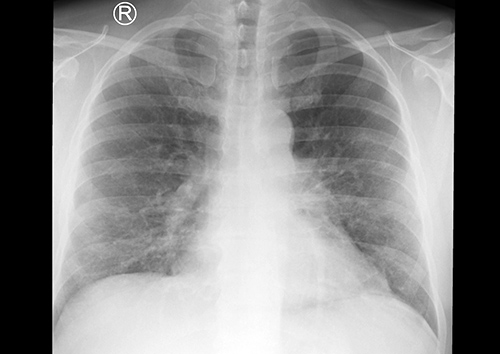

Při příjmu na Kliniku infekčních nemocí byl pacient afebrilní, orientační neurologický nález v normě, hrdlo klidné, fyzikální nález na orgánech fyziologický. Dominovala mírná dehydratace a námahová dušnost, saturace O2 měřená pulzním oxymetrem činila 95 %. V laboratorních náběrech byla prokázána výrazná elevace CRP (235 mg/l), ostatní nálezy byly nevýznamné: leukocyty 8,9 × 109/l; trombocyty 234 × 109/l; poměr polymorfonukleáry/lymfocyty 5,45; urea 3,1 mmol/l; kreatinin 71 µmol/l; AST 1,48 µkat/l; ALT 1,29 µkat/l; moč chemicky negativní. RTG vyšetření plic prokázalo infiltrativní, spíše intersticiální zánětlivé změny v dolních plicních polích a perihilózně vlevo (obr. 1). Na sonografii břicha byla patrná jenom hraniční velikost sleziny, ostatní nález v mezích normy.

RTG S+P   Obr. 1: Skiagram plic: Srdeční stín s mírnou dilatací. Oboustranně transparence plicního parenchymu bez výraznější asymetrie, v horních polích zachovalá a bez ložiskových i čerstvých infiltrativních změn, v dolních polích lehce nižší a bronchovaskulární kresba retikulárního charakteru. Obraz infiltrativních, spíše intersticiálních zánětlivých změn v dolních plicních polích, zejména perihilózně vlevo.